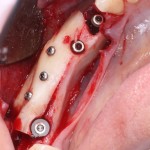

Имплантация и остеопластика: вместе или врозь? Часть II плюс Ankylos, плюс Geistlich